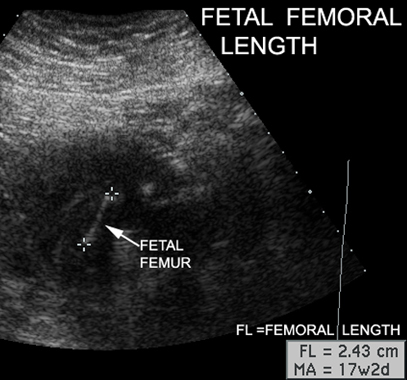

Identify fetal femur. How do you use the length of fetal femur. Answer

Placenta, Tibia, Femur